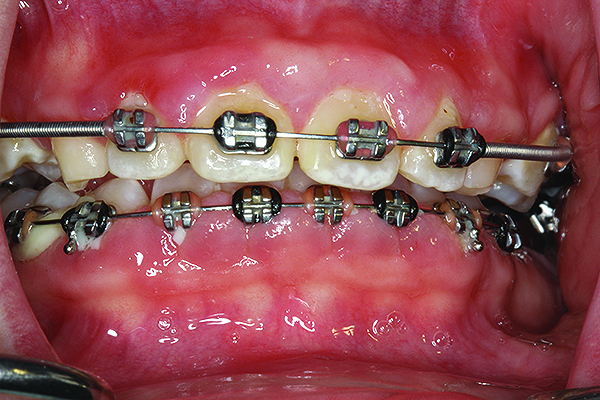

Fig 3. Gross caries and severe periodontitis in a patient presenting with a chief complaint of halitosis.

Figure 3

Clinical and radiographic examinations are essential to diagnose dental pathologies. Carious lesions, defective restorations, or fractured cusps, restorations or teeth (Figure 2 and Figure 3) can be sources of malodor both due to food impaction and foul odor associated with necrotic pulp tissue in cases of severe decay.10 Proper excavation, restorations, and regular follow-up are essential for the successful treatment of these patients. Areas of food impaction should be evaluated for restorations to close the embrasure space. Proper instruction of home care via dental floss and/or interproximal brushes is also required. An individual prone to caries as the source of malodor may also benefit from the adjunctive use of a fluoride-containing mouthrinse or toothpaste.

A rotten egg or cabbage smell is indicative of VSC being the main cause of halitosis. These compounds are usually associated with periodontal disease (Figure 3 and Figure 4) and/or tongue coating. Patients suffering from periodontitis or peri-implantitis require professional periodontal treatment in order to eliminate periodontal pathogens.5 Following a professional scaling and root planing appointment, Gram-negative anaerobic bacteria responsible for causing periodontal disease and producing VSC are reduced.5 This, in turn, encourages repopulation with Gram-positive cocci and bacterial rods that are associated with oral health.